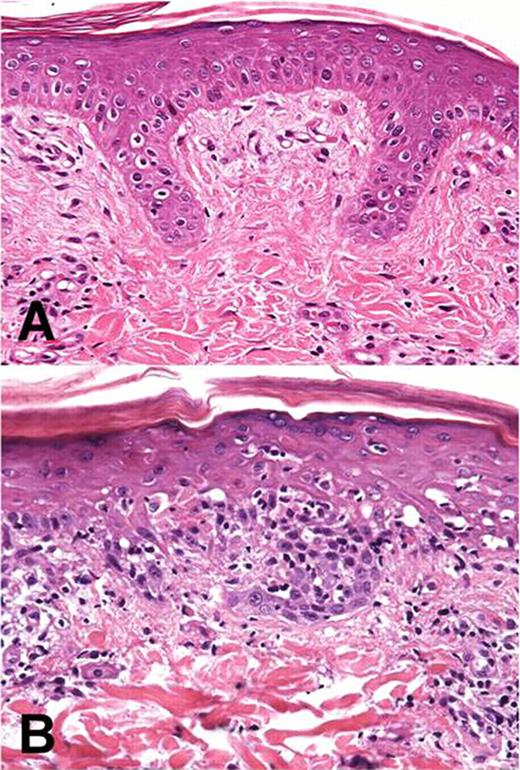

Graft-versus-host disease (GVHD) remains a frequent complication of hematopoietic cell transplantation with skin being a principal target organ. Murine models have provided some insight into the mechanisms of this complex disease process. However, mouse skin differs from human skin, and results of studies in rodents may not translate well to the clinic. Miniature swine is a well-recognized animal model for preclinical studies of skin including dermal toxicology, transdermal drug delivery and wound healing. Unlike skin of rodents, dogs or non-human primates, porcine skin is similar to human skin in terms of structure of epidermal rete ridges (Figure 1A), hair follicle structure and density, and presence of sweat glands and subcutaneous fat.

In this study we assess histologically the manifestations of acute GVHD in both donor and host skin and compare it to typical histological manifestations of acute GVHD observed in patients. Specifically, recipient skin developed superficial lymphoid infiltrates that progressed to confluence along the dermal-epidermal junction by day 21. These infiltrates were associated with intraepidermal migration, prominent basal cell layer keratinocyte apoptosis, and satellitosis virtually indistinguishable from grade 3–4 human cutaneous acute GVHD (Figure 1B). Superficial portions of hair follicles were involved, as also seen in human disease. Of interest, mild disease was detected in the donor skin grafts by day 62 post-DLI, where selective lymphoid infiltration in the tips of the epidermal rete ridges and in association with target cell apoptosis/satellitosis was documented, a finding remarkably similar to early targeting events in humans.

Comparison of normal porcine skin (A) resembling epidermal and dermal layers of human integument, and (B) recipient skin 34 days post DLI, showing brisk superficial lymphoid infiltrate associated with basal layer epidermal apoptosis.